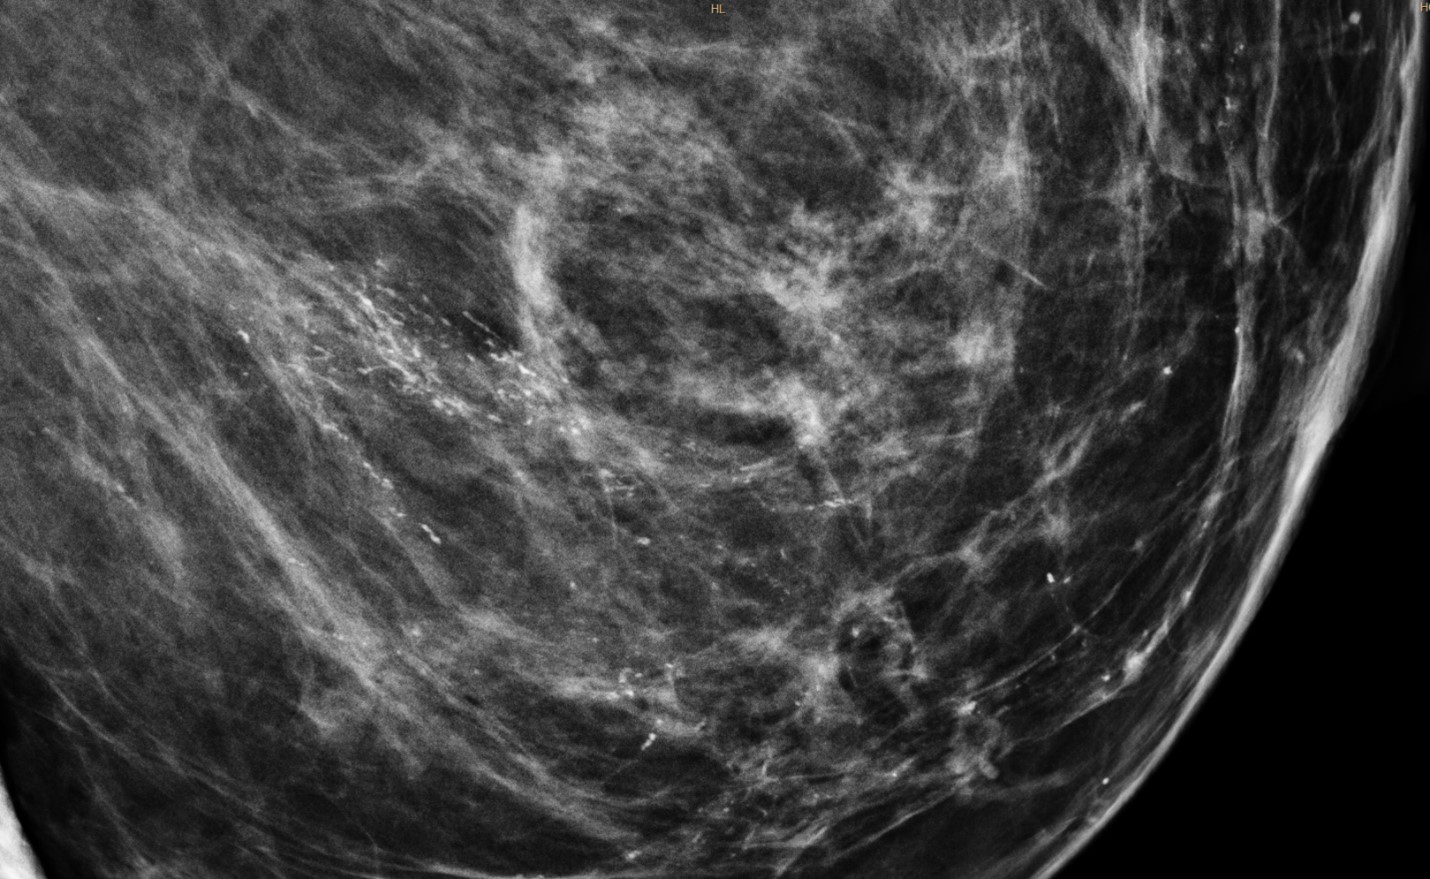

- Chụp X-quang vú (mammography): là phương pháp dùng một lượng tia X nhỏ để ghi lại hình ảnh của tuyến vú nhằm phát hiện những bất thường hoặc những khối u vú, đặc biệt là các vi vôi hóa khi chưa sờ thấy u qua thăm khám.

Hình minh họa: tổn thương vi vôi hóa ở vú phát hiện khi chụp X-quang